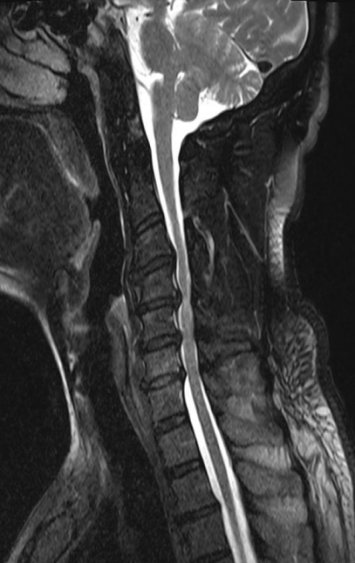

经我院骨病中心脊柱外科医师详细询问病史及查体,并完善相关辅助检查。X线片提示:颈椎生理曲度变直,颈椎骨质增生;CT、MRI提示:颈3/4、颈6/7椎间盘突出,颈4/5椎间盘膨出伴右后突出,右侧椎间孔及椎管狭窄,颈5/6椎间盘膨出伴左后突出,左侧椎间孔及椎管狭窄。综合患者临床症状,最终诊断为混合型颈椎病。

在通过沟通后,骨病中心主任袁毅团队为患者施行显微镜辅助下颈椎前路颈椎间盘切除+椎间植骨融合内固定术(ACDF)。术中在显微镜的辅助下,清楚显露解剖结构,彻底切除椎间盘、骨赘、减压椎间孔,切除后纵韧带,解除脊髓神经压迫,术中出血约20ml。